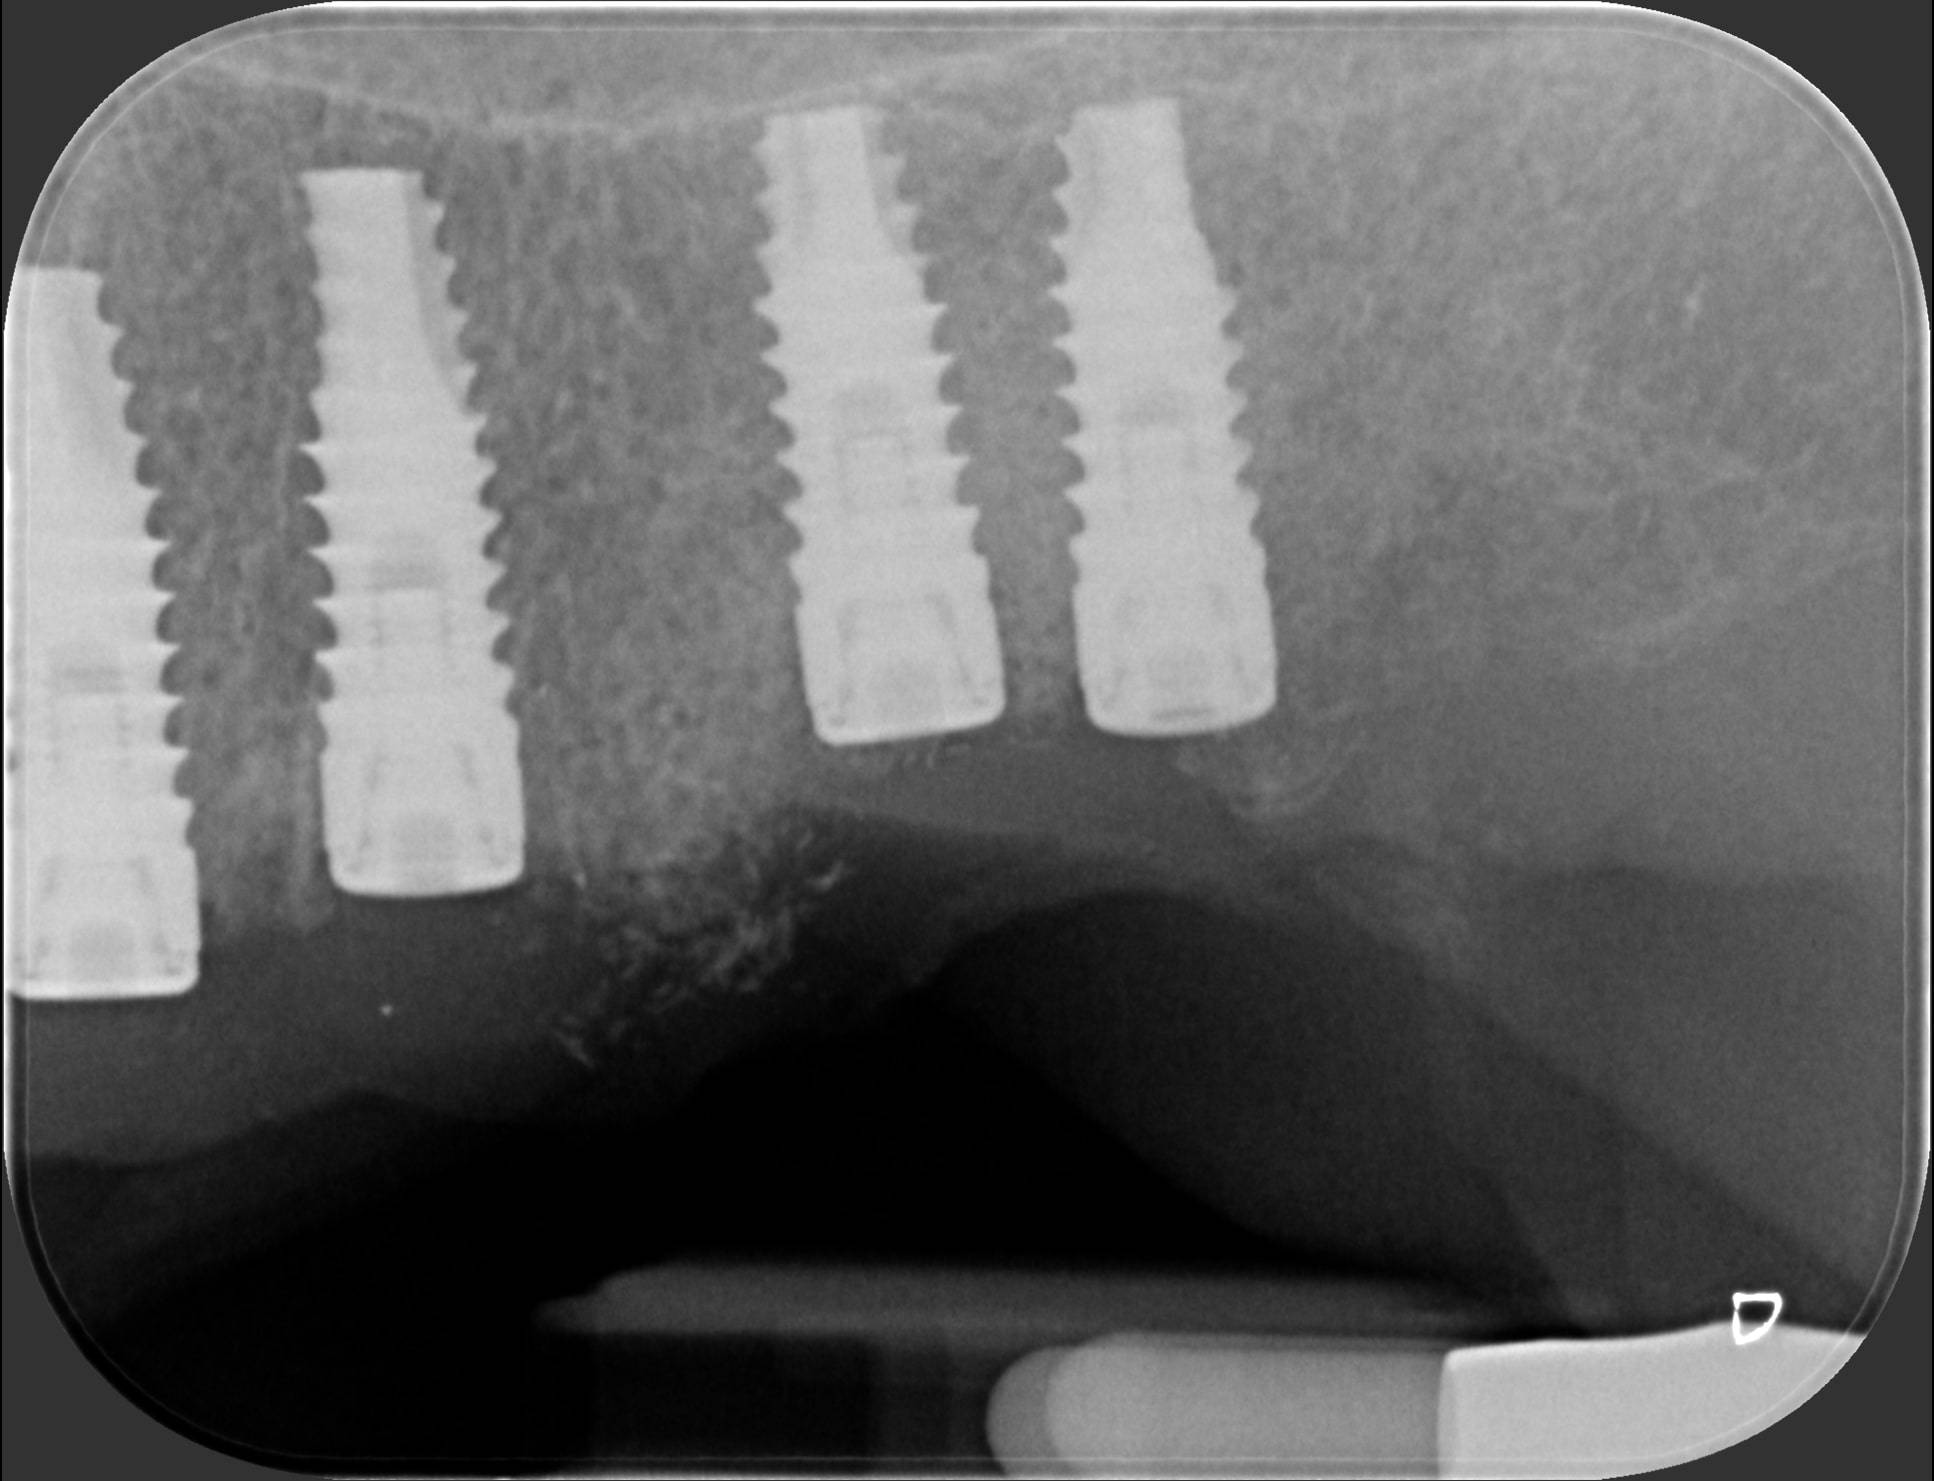

Un laboratorio specializzato ha creato una dima in resina nella quale ci sono degli anelli metallici che mi hanno guidato a posizionare gli impianti esattamente secondo quanto programmato al computer. Nella prima foto puoi vedere com’è fatta la dima: si vedono chiaramente 6 anelli esagonali (2 a destra della paziente e 4 a sinistra), dentro cui ho inserito le frese per creare la strada agli impianti, che ho avvitato poco dopo. Una volta posizionata la dima sui denti, è facilissimo e veloce posizionare gli impianti seguendo le guide metalliche. Infatti nelle foto successive si vedono le radiografie degli impianti messi dentro l’osso in modo perfettamente paralleli fra loro, 2 a destra e 4 a sinistra, proprio come da progettazione virtuale. La profondità, l’angolazione e la distanza tra i vari impianti sono state calcolate attraverso il computer prima ancora di eseguire l’intervento, con una precisione che è difficile raggiungere con un intervento a mano libera. Le radiografie parlano da sole. Dott. Fabio Ballestrasse, Besana Brianza (MB).